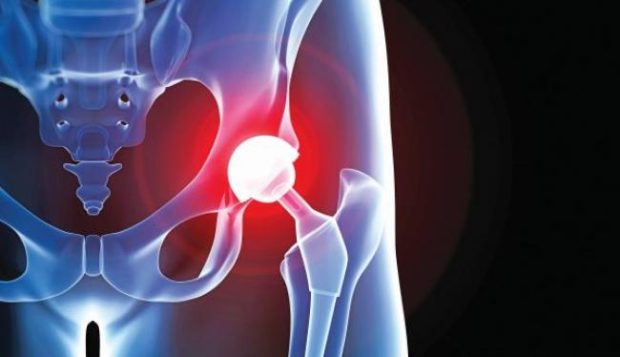

Μύες και τένοντες μένουν ανέπαφοι κατά τη διάρκεια της αρθροπλαστικής

Μύες και τένοντες μένουν ανέπαφοι κατά τη διάρκεια της αρθροπλαστικής

Μια νέα, ελάχιστης επεμβατικότητας χειρουργική τεχνική για την ολική αρθροπλαστική του ισχίου, με τη διατήρηση όλων των μυών και των τενόντων, τα οποία κόβονταν με την παραδοσιακή χειρουργική επέμβαση, υπόσχεται γρηγορότερη αποκατάσταση του ασθενούς, λιγότερο πόνο και μείωση πολλών από τις πιθανές χειρουργικές επιπλοκές.

«Με την τεχνική Superpath κανένας μυς δεν κόβεται ή αποκολλάται από το οστό του μηριαίου, παρά μόνο απωθείται για τη δημιουργία ενός μικρού “παραθύρου”, από όπου αντικαθίσταται η άρθρωση του ισχίου» εξηγεί ο Κωνσταντίνος Σαράντος, ορθοπεδικός χειρουργός στο πανεπιστημιακό νοσοκομείο του Coventry and Warwickshire, στη Βρετανία.

Οπως αναφέρει σε συνέντευξή του στο Αθηναϊκό – Μακεδονικό Πρακτορείο Ειδήσεων, είναι σημαντικό να γίνει κατανοητό ότι η χειρουργική επέμβαση με προστασία των μαλακών μορίων δεν σημαίνει μόνο μικρή τομή, αλλά και διατήρηση και προστασία των σημαντικών μυών και τενόντων γύρω από το ισχίο.

Ετσι ο ασθενής μπορεί να κινητοποιηθεί σε λίγες μέρες ή ακόμα και ώρες μετά την επέμβαση. Πολλοί ασθενείς είναι ικανοί να πάρουν εξιτήριο χωρίς τυπικούς περιορισμούς, όπως για παράδειγμα να μη σταυρώνουν τα πόδια. Με τη μέθοδο Superpath δεν γίνεται χειρουργική εξάρθρωση του ισχίου. Το ζητούμενο σε κάθε επιτυχημένη επέμβαση με προστασία των μαλακών μορίων είναι η αποφυγή του τραυματισμού τους.

Το ότι δεν εξαρθρώνεται χειρουργικά το ισχίο σημαίνει πολύ λίγους τραυματισμούς των μυών και τενόντων που το περιβάλλουν. Με αυτήν τη χειρουργική τεχνική η πρόθεση τοποθετείται μέσα στο σώμα χωρίς το ισχίο να στρέφεται σε μη φυσικές θέσεις, όπως συμβαίνει με άλλες τεχνικές. Αποφεύγοντας τη διατομή και την αποκόλληση των μυών και των τενόντων ελαχιστοποιούνται το τραύμα, ο πόνος και η αιμορραγία.

Ετσι μένουν ανέπαφα περισσότερα μαλακά μόρια και κυρίως οι έξω στροφείς του ισχίου και οι γλουτιαίοι μύες. Αυτοί οι μύες προλαμβάνουν την εξάρθρωση και επιτρέπουν φυσιολογική βάδιση, χωρίς ο ασθενής να κουτσαίνει, όπως συμβαίνει συχνά με τις παραδοσιακές τεχνικές.